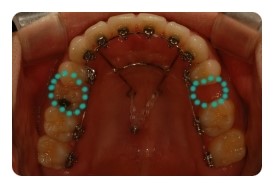

( 상악비교 )

▲ 발치 전 - 왼쪽유치 1차삭제, 오른쪽영구치 발치 예정

▲ 6월 - 스크류식립 후 본격적으로 상악당기기 1개월차

▲ 8월 - 3개월차

▲ 10월 - 5개월차

조신하지못한 저의 잦은 어금니 브라켓탈락 ㅠㅠ 에도 불구하고 잘 이동하고 잇는듯해요